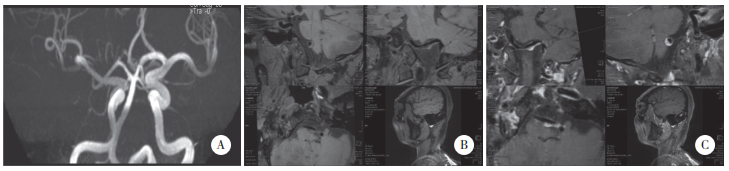

并发组BA直径、BA长度、VA颅内段长度长于未并发组,BA分叉高度分级≥2级、BA偏移度分级≥2级比例高于未并发组(P<0.05),见表 2,图 1、2。

| A, MRA showing a tortuous and dilated vertebrobasilar artery; B, vascular wall imaging showing mild eccentric thickening of the local wall of the basilar artery; C, enhanced imaging of the vascular wall showing mild enhancement of the wall. 图 1 VBD未并发后循环ACI患者MR-VWI图 Fig.1 MR-VWI image of VBD patients without posterior circulation ACI |